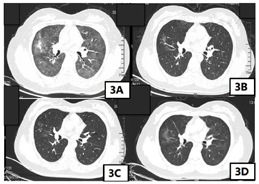

患者诊断为免疫检查点抑制剂相关性肺炎3级,根据《CSCO免疫检查点抑制剂相关肺炎的临床诊治建议》,对于2~3级的CIP,推荐使用1~2 mg/(kg·d)泼尼松的等效剂量激素治疗,可选择口服或静脉激素(泼尼松或甲泼尼龙),对于更严重者或急性病程者,首选静脉激素。对于激素的减量方法,推荐在观察到起始剂量[1~2 mg/(kg·d)]激素起效后(48~72 h),继续维持原剂量使用至7~14 d,随后开始逐步减量,控制整体疗程在6~8周,一般不超过12周。足量激素治疗时间建议最长不超过3周[3]。激素使用过程中需要注意监测相应的毒副作用。患者体重为65 kg,推荐使用65~130 mg泼尼松的等效剂量激素治疗,患者2020年9月11日—2020年9月13日甲泼尼龙注射液80 mg静脉输液治疗,患者症状明显缓解,无呼吸困难,活动后无明显气短,可自行上下楼梯,因患者较年轻,现放疗后人工绝经,患者及家属非常担忧骨质疏松,股骨头坏死等副作用,要求激素减量,2020年9月14日—2020年9月16日予甲泼尼龙注射液60 mg静脉输液治疗,2020年9月17日—2020年9月19日予甲泼尼龙注射液40mg静脉输液治疗,患者已无免疫检查点抑制剂相关性肺炎症状,改为口服激素治疗,2020年9月20日—2020年9月23日予美卓乐(甲泼尼龙片)8片口服(32 mg=泼尼松的等效剂量40 mg)治疗,2020年9月24日—2020年9月30日予美卓乐6片口服(24 mg=泼尼松的等效剂量30 mg),2020年10月1日—2020年10月7日予美卓乐4片口服(16 mg=泼尼松的等效剂量20 mg),2020年10月8日—2020年10月14日予美卓乐2片口服(8 mg=泼尼松的等效剂量10 mg),2020年10月15日—2020年10月21日予美卓乐2片口服(4 mg=泼尼松的等效剂量5 mg),共使用糖皮质激素治疗6周。其间复查胸部CT模糊斑片影较前明显缓解(图3)。糖皮质激素治疗期间予患者补充钙剂、维生素D3,骨化醇预防骨质疏松,质子泵抑制剂,膜固思达,洁维乐保护胃肠道黏膜,预防应激性溃疡。同时监测感染相关指标,监测血压、血糖、电解质等,患者大便真菌涂片及咽真菌涂片找到真菌孢子,予使用大扶康抗真菌感染治疗。